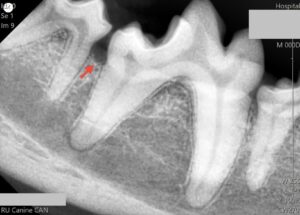

別症例(歯科レントゲンでの比較)

軽度歯周病

プロービングを行い、歯周ポケットの有無を確認した後、歯科専用のレントゲンを用いて歯周組織の状態を確認し、必要に応じて抜歯処置もしくはルートプレーニングやキュレッタージにより保存治療を行います。